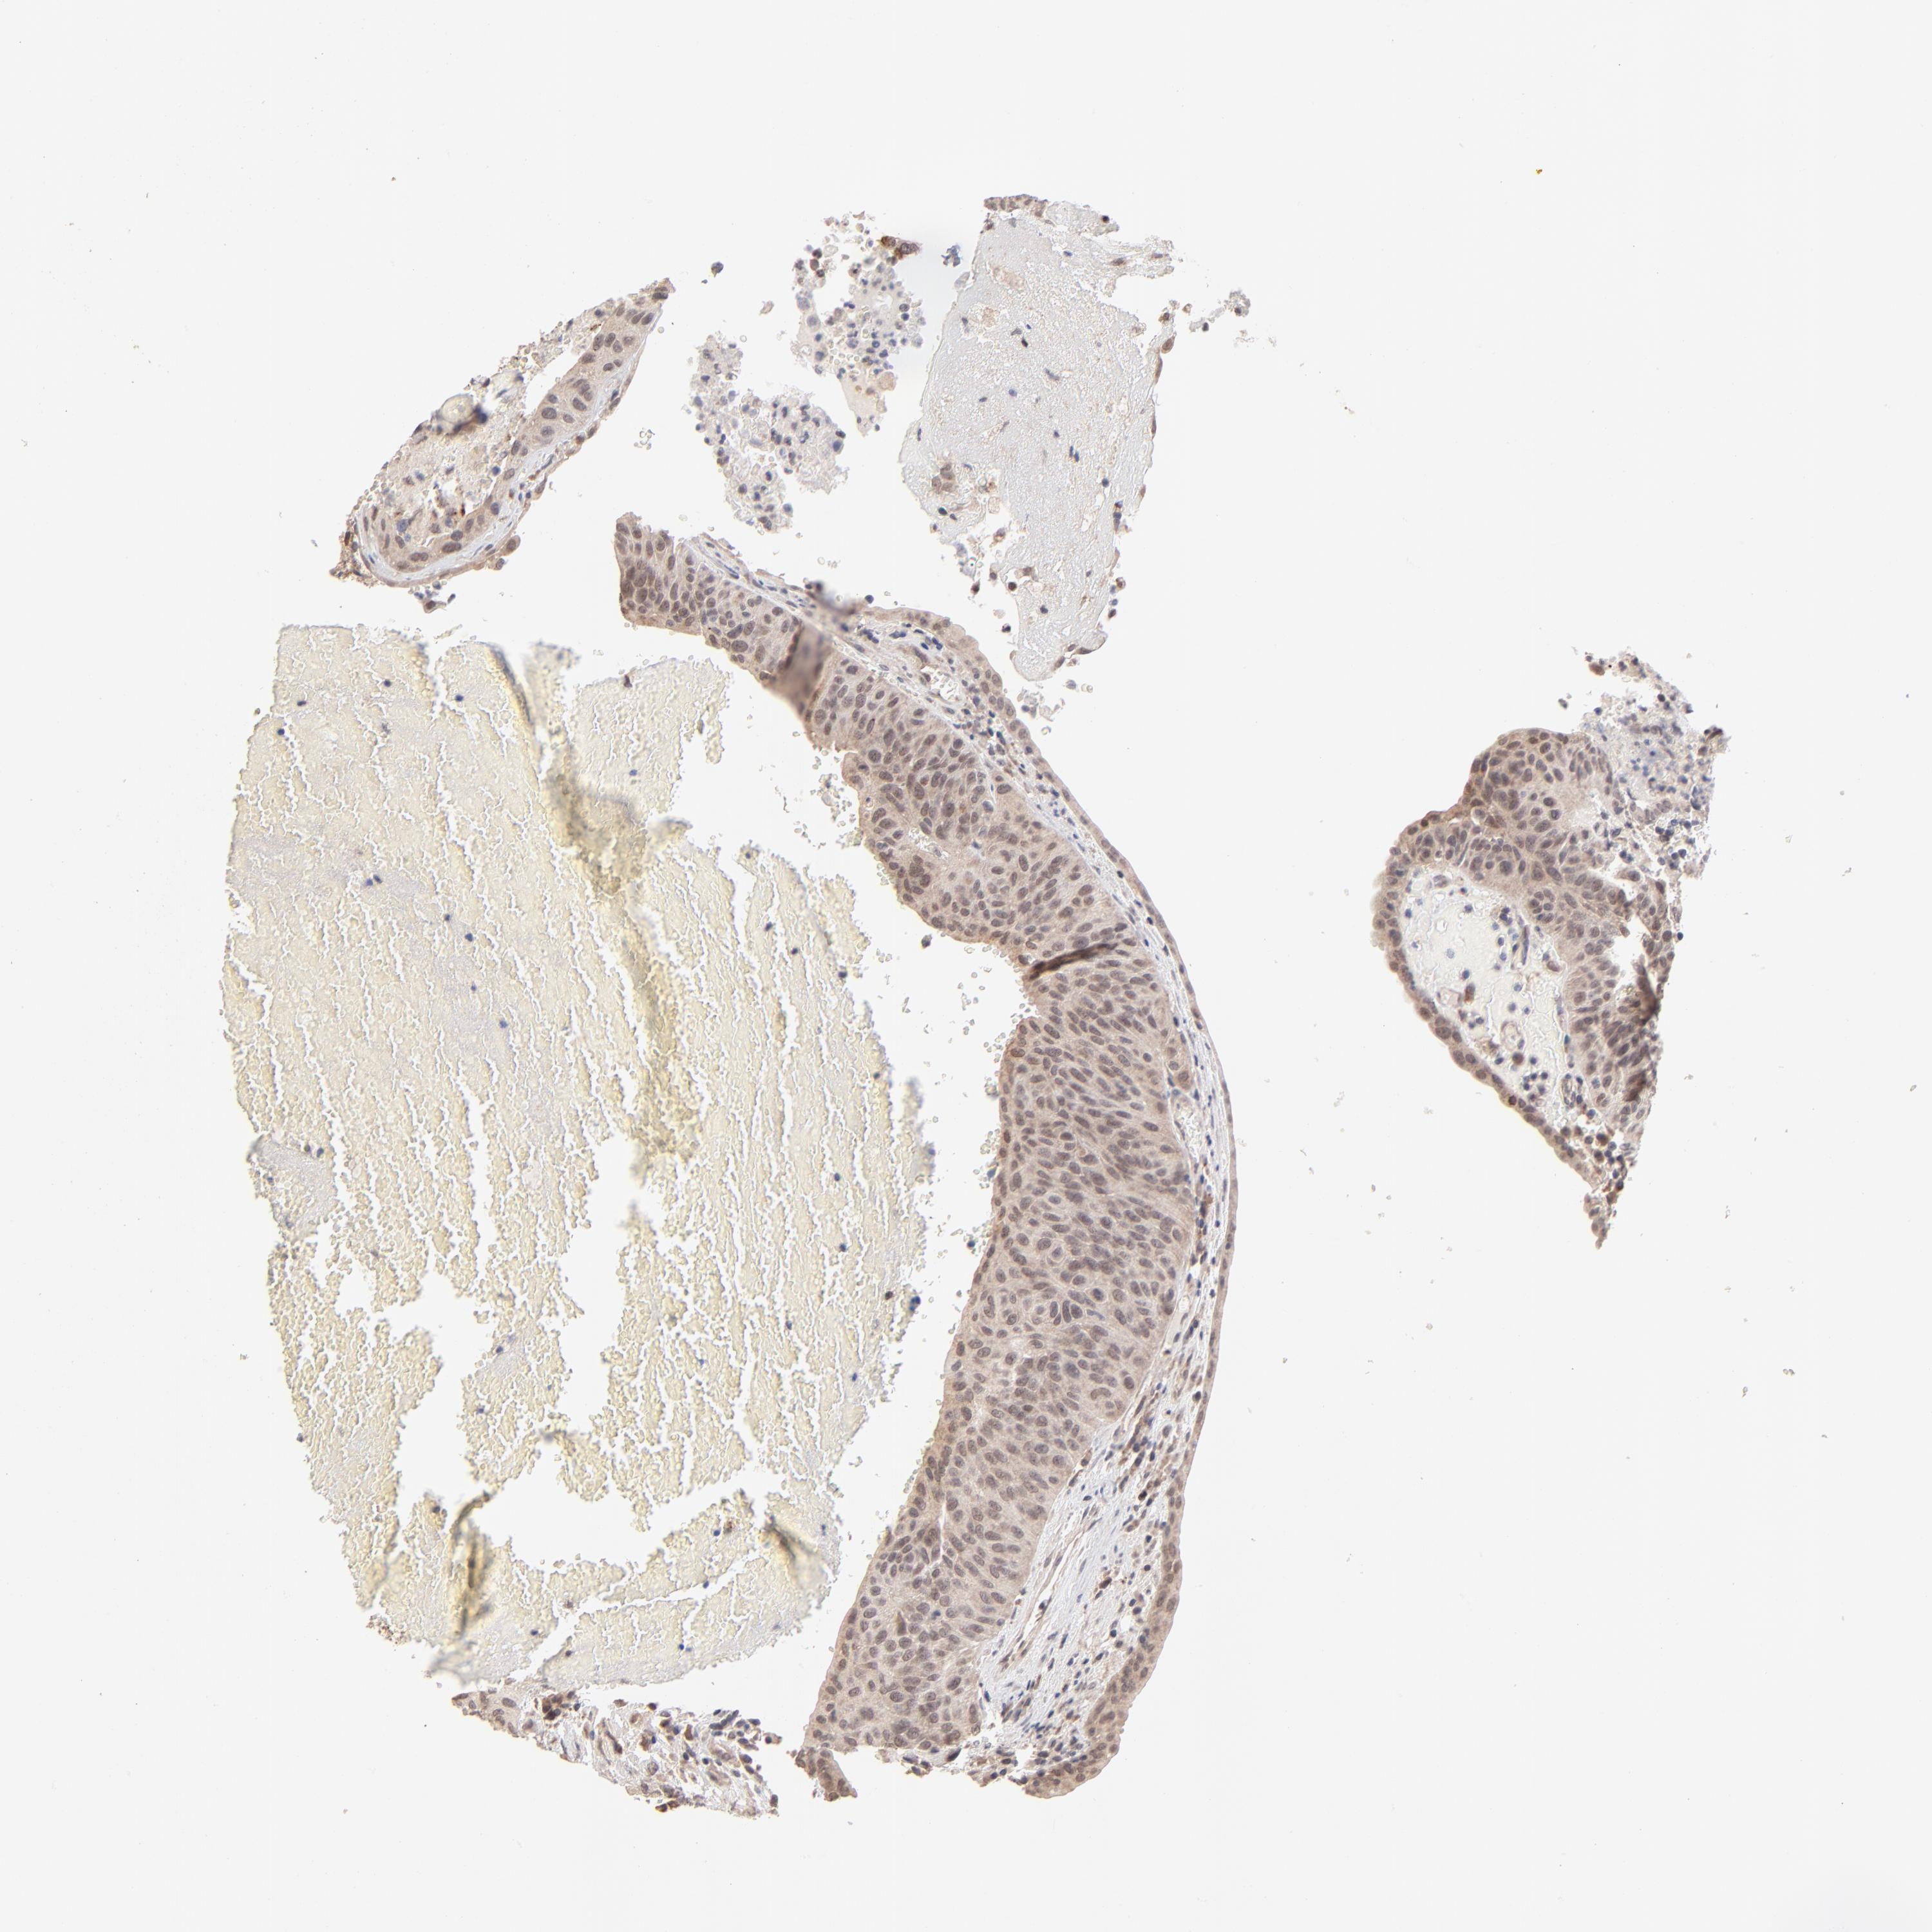

UROTHELIAL CANCER - Protein expressioni

A mouse-over function shows sample information and annotation data. Click on an image to view it in a full screen mode. Samples can be filtered based on level of antibody staining by selecting one or several of the following categories: high, medium, low and not detected. The assay and annotation is described here.

Note that samples used for immunohistochemistry by the Human Protein Atlas do not correspond to samples in the TCGA dataset.

Antibody stainingi

Antibody staining in the annotated cell types in the current human tissue is reported as not detected, low, medium, or high, based on conventional immunohistochemistry profiling in selected tissues. This score is based on the combination of the staining intensity and fraction of stained cells.

Each image is clickable and will lead to virtual microscopy that enables deeper exploration of all samples and also displays staining intensity scores, fraction scores and subcellular localization as well as patient and tissue information for each sample.

Antibody HPA003413

Staining

High

Medium

Low

Not detected

Intensity

Strong

Moderate

Weak

Negative

Quantity

>75%

75%-25%

<25%

None

Location

Nuclear

Cytoplasmic/membranous

Cytoplasmic/membranous,nuclear

Urothelial carcinoma, High grade

Urothelial carcinoma, Low grade